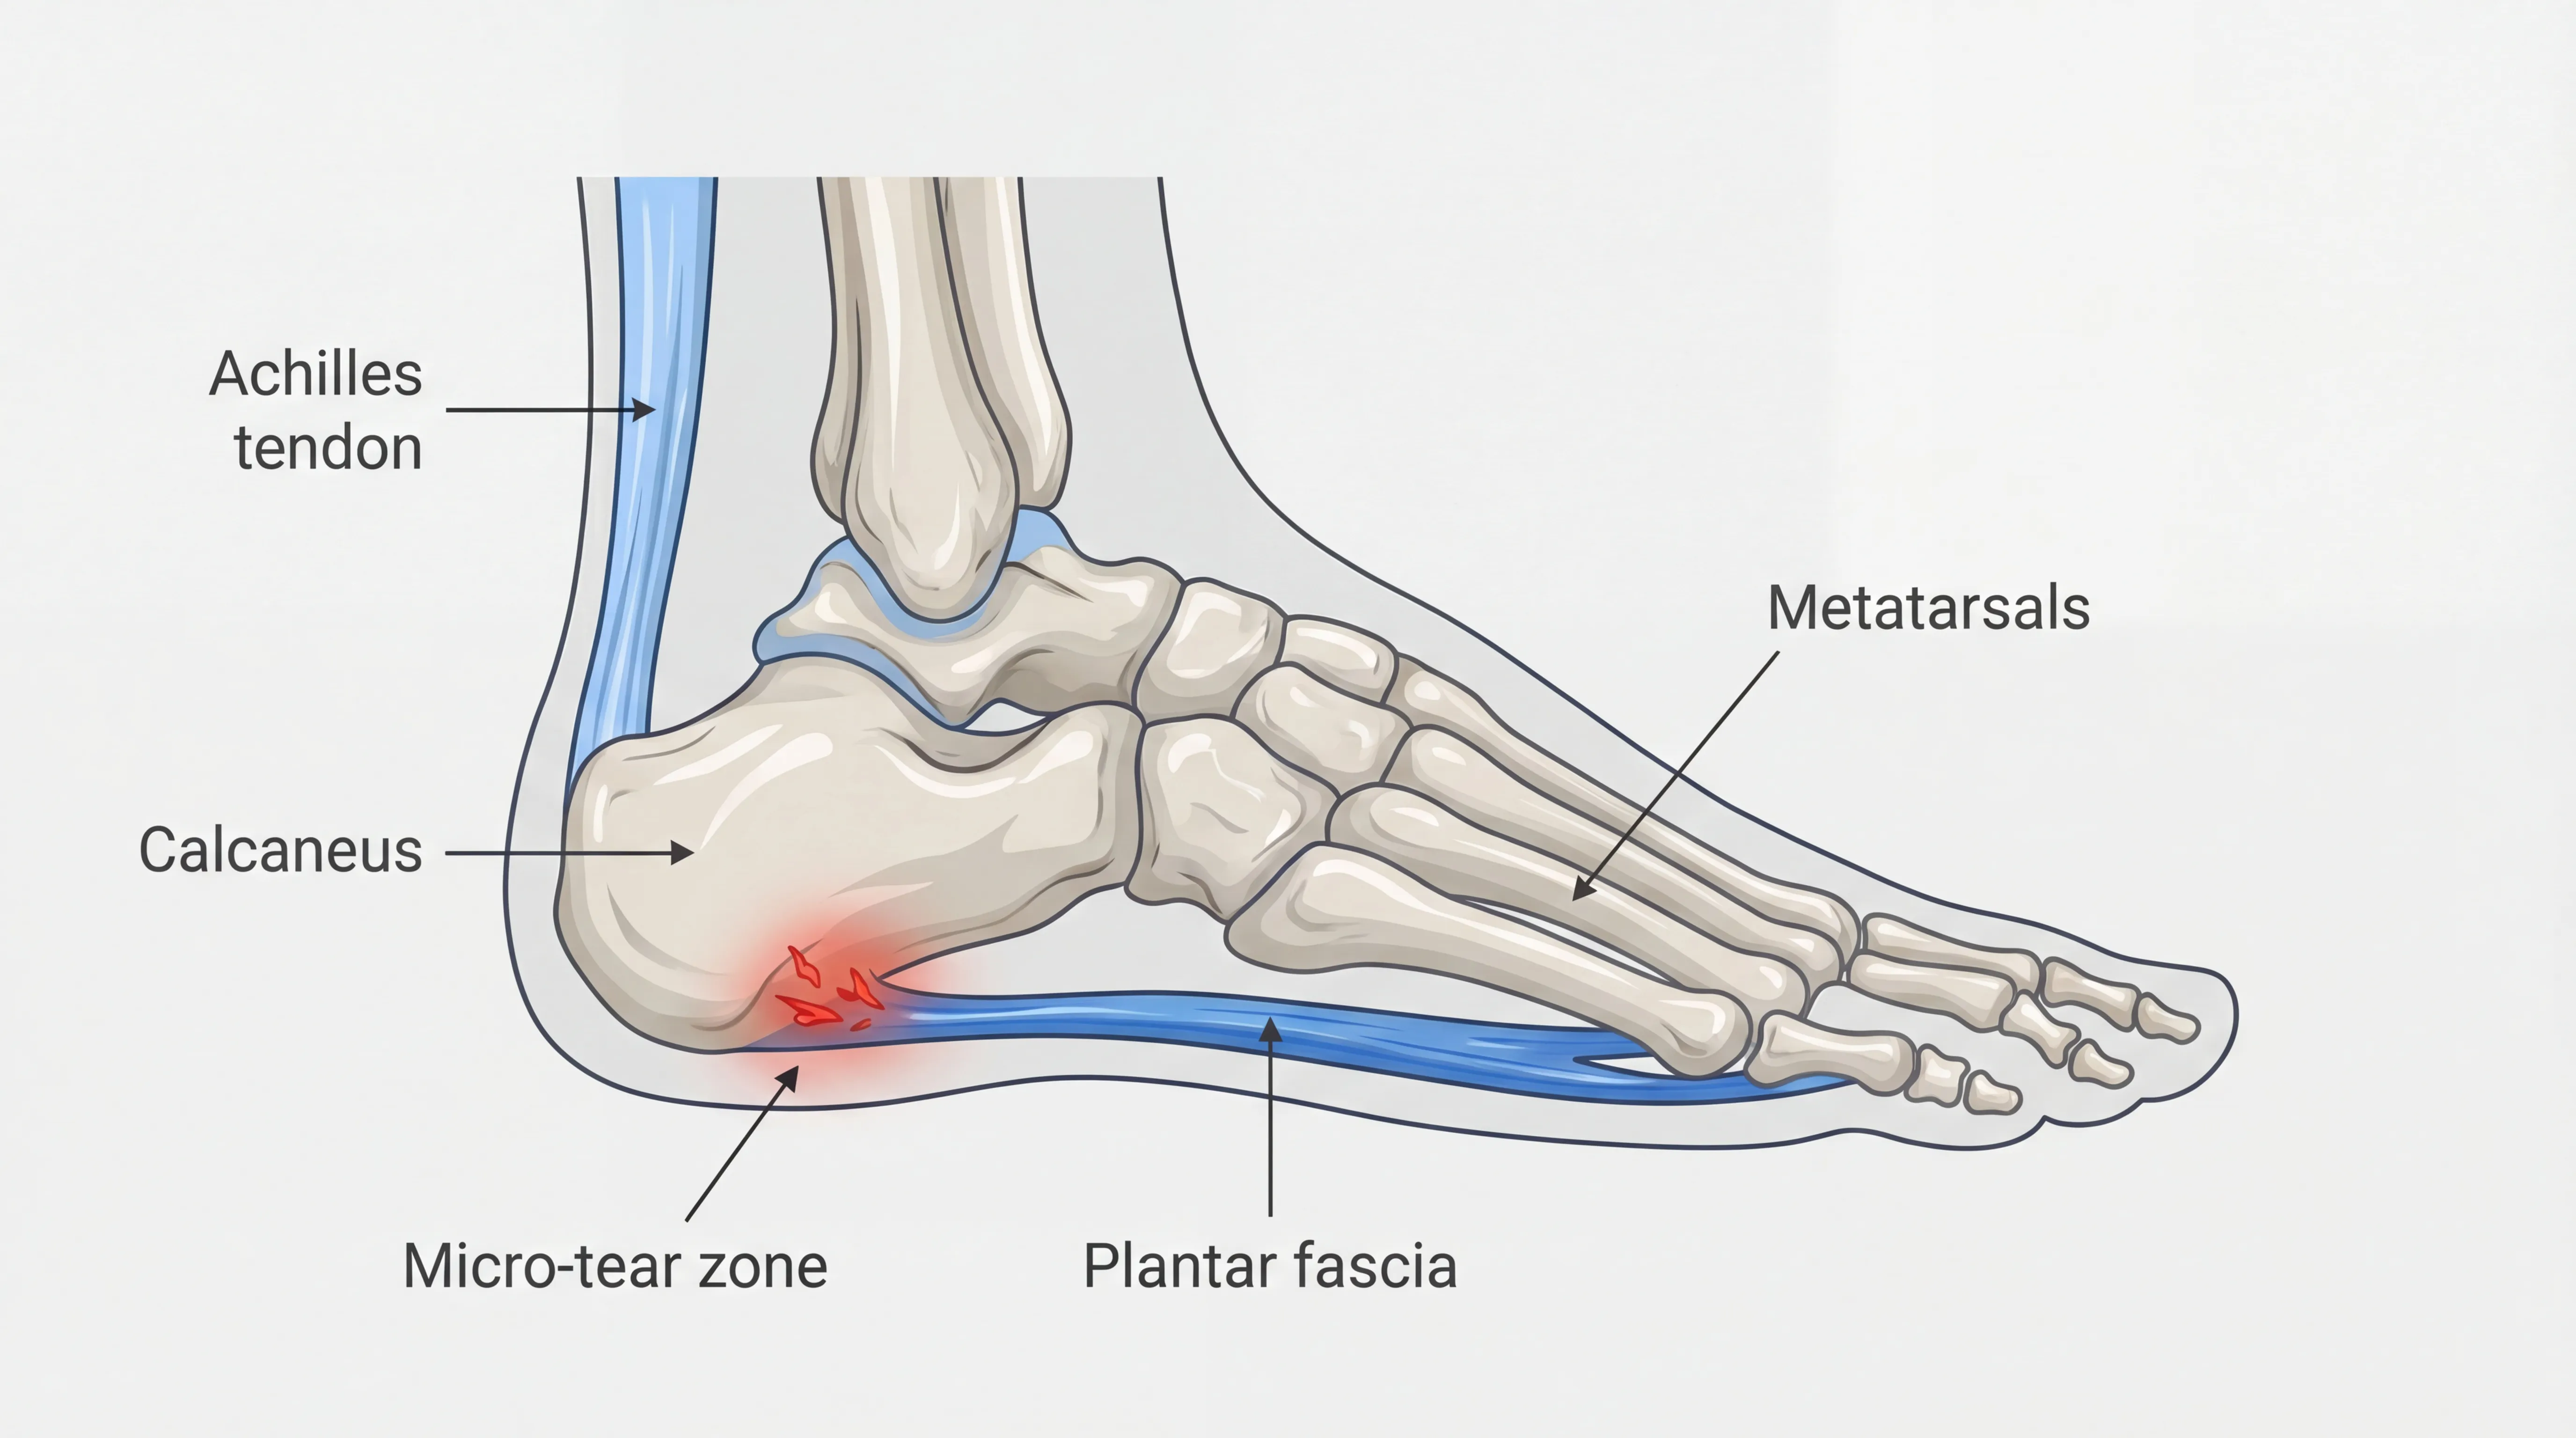

Plantar fasciitis is a degenerative condition of the plantar fascia, the thick band of tissue that runs along the bottom of your foot from the heel bone to the toes.[3] This tissue supports your arch and absorbs shock with every step you take.

When overstressed, the fascia develops small tears and stiffens. Overnight, your feet relax into a pointed position that lets the damaged tissue contract. Your first morning step forces it to stretch suddenly against that tightness, which is why the pain hits hardest when you get out of bed.

Plantar fasciitis develops when repeated mechanical stress creates small tears in the plantar fascia tissue. Tight calf muscles and inadequate footwear increase tension on the fascia and contribute to chronic heel pain over time.

- Tight calf muscles and Achilles tendons that pull on the fascia from above (see our Achilles tendonitis guide for the full kinetic chain)

Plantar fasciitis is pain from the soft tissue (the fascia); a heel spur is a bony calcium deposit on the heel bone. They often coexist but require different attention.